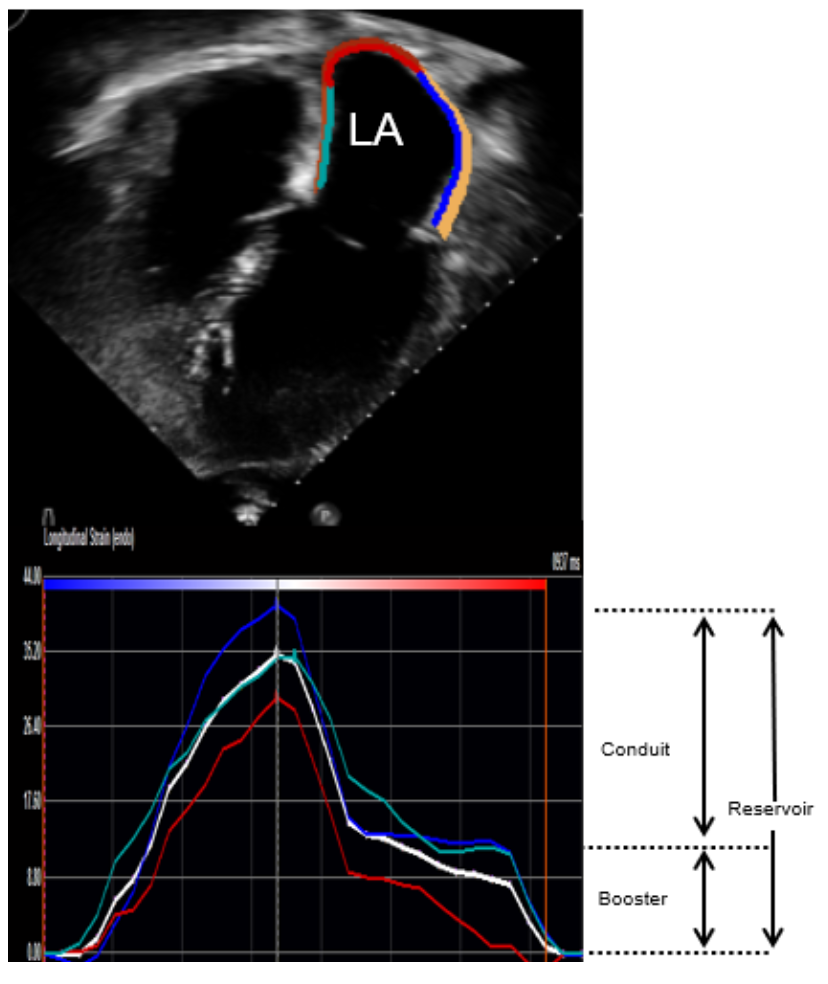

Echocardiographic assessment of LA function. The procedural details for speckle tracking strain imaging in our laboratory have been described.18,19 In brief, LA strain was obtained using Vivid E9 and E95 (General Electric Co) with M5S and M5Sc-D transducers (1.5-4.6 MHz) at a frame rate of 40-80 Hz, and these images were exported (DICOM) and then analyzed offline using TomTec (TomTec Imaging Systems). Adequate tracking by the software was visually verified and retraced if necessary until adequate tracking was achieved. LA reservoir strain, LA conduit strain, and LA booster strain were assessed using the QRS as the fiduciary point, as shown in Figure 2.

Correlation between the LA strain and LVEDP. LVEDP was measured in 112 patients (89%); the median LVEDP was 17 mm Hg (IQR, 14-20) and 61 of 112 patients (55%) had elevated LVEDP (>16 mm Hg). There was a modest correlation between LA reservoir strain and LVEDP (r = -0.39; P<.001) and between LA booster strain and LVEDP (r = -0.33; P<.01) (Figure 2). Of the 112 patients, 103 were in sinus rhythm while 6 patients were in atrial fibrillation and 3 patients had right ventricular pacing at the time of echocardiogram. We observed a modest correlation between LA reservoir strain and LVEDP (r = -0.43; P<.001) and between LA booster strain and LVEDP (r = -0.36; P<.001) among the patients in sinus rhythm. Similar analyses were not performed in the patients with atrial fibrillation or right ventricular pacing because of small sample size.